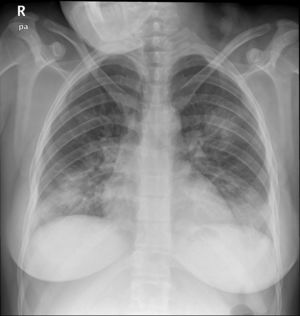

Case reportA 24-year-old pregnant woman at term (height: 1.61 m; weight: 68 kg) was admitted with a 3-day history of fever, cough and dyspnoea. Chest X-ray showed a pattern of bilateral interstitial pneumonia in the middle and lower fields (Fig. 1) and reverse transcriptase polymerase chain reaction (RT-PCR) for COVID-19 was positive. Treatment with hydroxychloroquine, azithromycin, ceftriaxone, lopinavir/ritonavir, and enoxaparin was started.

A new chest X-ray showed worsening (Fig. 2) and labs showed a pro-inflammatory state with IL-6: 151 pg/mL, PCR: 13.4 mg/dl, and procalcitonin: 9.3 ng/mL, so tocilizumab was administered. Respiratory mechanics improved, permitting PEEP to be decreased and switching to pressure support ventilation on the third day. Levetirazetam was started due to a suspicion that the neurological deterioration could have been caused by a seizure. An electroencephalogram (EEG) showed a marked slowing pattern and occasional triphasic waves that were more marked at the left temporal level, calling for investigation of a possible underlying lesion. No epileptiform activity was observed. Daily sedation windows were performed, connecting the patient on the fourth day and allowing extubation. During her stay, she presented an isolated episode of hypertension (HT) that responded to 25 mg of iv urapidil.

Anteroposterior chest X-ray in supine position: radiological worsening compared to Fig. 1. Lower lung volumes, increased bibasal opacities. Moderate-severe radiological involvement.